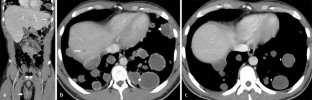

Wir berichten über einen 31-jährigen Patienten mit einer klinisch manifesten Hyperthyreose infolge eines β-HCG produzierenden metastasierten Keimzelltumors im rechten Hoden. Nach Einleitung einer Chemotherapie kam es parallel zur Remission des Tumors mit deutlichem Abfall des β-HCG zur Normalisierung der Schilddrüsenlaborparameter.

We report on a 31-year-old male patient with overt clinical hyperthyroidism resulting of a hCG-producing metastasized germ cell tumor of the right testicle. After initiation of chemotherapy, thyroid function normalized in parallel to the tumor’s remission with marked decrease of hCG levels.

Abb. 1